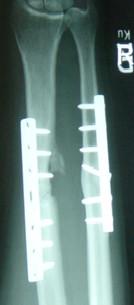

自体骨移植与脱矿骨基质用于长骨不愈合的内固定治疗

Autologous bone graft versus demineralized bone matrix in internal fixation of ununited long bones.

Non-unions are severe complications in orthopaedic trauma care and occur in 10% of all fractures. The golden standard for the treatment of ununited fractures includes open reduction and internal fixation (ORIF) as well as augmentation with autologous-bone-grafting. However, there is morbidity associated with the bone-graft donor site and some patients offer limited quantity or quality of autologous-bone graft material. Since allogene bone-grafts are introduced on the market, this comparative study aims to evaluate healing characteristics of ununited bones treated with ORIF combined with either iliac-crest-autologous-bone-grafting (ICABG) or demineralized-bone-matrix (DBM).

From 2000 to 2006 out of sixty-two consecutive patients with non-unions presenting at our Level I Trauma Center, twenty patients had ununited diaphyseal fractures of long bones and were treated by ORIF combined either by ICABG- (n = 10) or DBM-augmentation (n = 10). At the time of index-operation, patients of the DBM-group had a higher level of comorbidity (ASA-value: p = 0.014). Mean duration of follow-up was 56.6 months (ICABG-group) and 41.2 months (DBM-group). All patients were clinically and radiographically assessed and adverse effects related to bone grafting were documented. The results showed that two non-unions augmented with ICABG failed osseous healing (20%) whereas all non-unions grafted by DBM showed successful consolidation during the first year after the index operation (p = 0.146). No early complications were documented in both groups but two patients of the ICABG-group suffered long-term problems at the donor site (20%) (p = 0.146). Pain intensity were comparable in both groups (p = 0.326). However, patients treated with DBM were more satisfied with the surgical procedure (p = 0.031).

With the use of DBM, the costs for augmentation of the non-union-site are more expensive compared to ICABG (calculated difference: 160 euro/case). Nevertheless, this study demonstrated that the application of DBM compared to ICABG led to an advanced outcome in the treatment of non-unions and simultaneously to a decreased quantity of adverse effects. Therefore we conclude that DBM should be offered as an alternative to ICABG, in particular to patients with elevated comorbidity and those with limited availability or reduced quality of autologous-bone graft material.

骨不连是骨科创伤治疗中的严重并发症,在所有骨折中发生率为10%。治疗骨不连的金标准包括切开复位内固定(ORIF)以及自体骨移植增强。然而,骨移植供区存在并发症,且一些患者的自体骨移植材料数量或质量有限。自从同种异体骨移植进入市场以来,这项对比研究旨在评估采用ORIF联合髂嵴自体骨移植(ICABG)或脱矿骨基质(DBM)治疗骨不连的愈合特征。

2000年至2006年期间,在我们的一级创伤中心连续收治的62例骨不连患者中,20例为长骨干骨不连,接受了ORIF联合ICABG(n = 10)或DBM增强(n = 10)治疗。在初次手术时,DBM组患者的合并症水平较高(美国麻醉医师协会评分:p = 0.014)。平均随访时间为56.6个月(ICABG组)和41.2个月(DBM组)。对所有患者进行了临床和影像学评估,并记录了与骨移植相关 的不良反应。结果显示,2例接受ICABG增强的骨不连未实现骨愈合(20%),而所有接受DBM移植的骨不连在初次手术后的第一年内均实现了成功愈合(p = 0.146)。两组均未记录到早期并发症,但ICABG组有2例患者在供区出现长期问题(20%)(p = 0.146)。两组的疼痛强度相当(p = 0.326)。然而,接受DBM治疗的患者对手术的满意度更高(p = 0.031)。

与ICABG相比,使用DBM增强骨不连部位的成本更高(计算差异:160欧元/例)。然而,本研究表明,与ICABG相比,应用DBM在治疗骨不连方面能带来更好的结果,同时不良反应数量减少。因此,我们得出结论,应将DBM作为ICABG的替代方案提供给患者,特别是合并症较高以及自体骨移植材料可用性有限或质量较差 的患者。